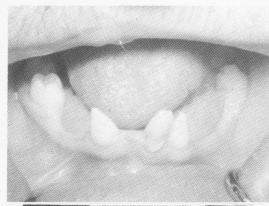

The patient, a 17-year-old boy, was depressed and despondent because of his cleft palate and hare lip. His remaining mandibular teeth were three right atypically shaped molars, a left second molar, and three anterior peg-shaped incisors that were severely malpositioned (Fig. 15-1). His upper teeth on the left side consisted of an atypically peg-shaped second bicuspid and two tapered molars, and on the right side a tapered second bicuspid and a molar (Fig. 15-2). The patient had been wearing a full upper acrylic denture with holes in it corresponding to the remaining molar teeth (Fig. 15-3).

Fig. 15-1. A, The lower teeth were peg-shaped and flared out from one another. B, Maxillary and mandibular study casts. No teeth existed in the maxilla anterior to the atypically shaped molars on each side.

A

B

1 Peg-shaped, flared out lower teeth, implant considerations